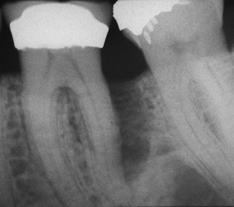

• - Fig. 1 Fig. 2 Fig. 3

• - Fig 2. X-ray 6 months following GTR treatment shows bony fill (healing).